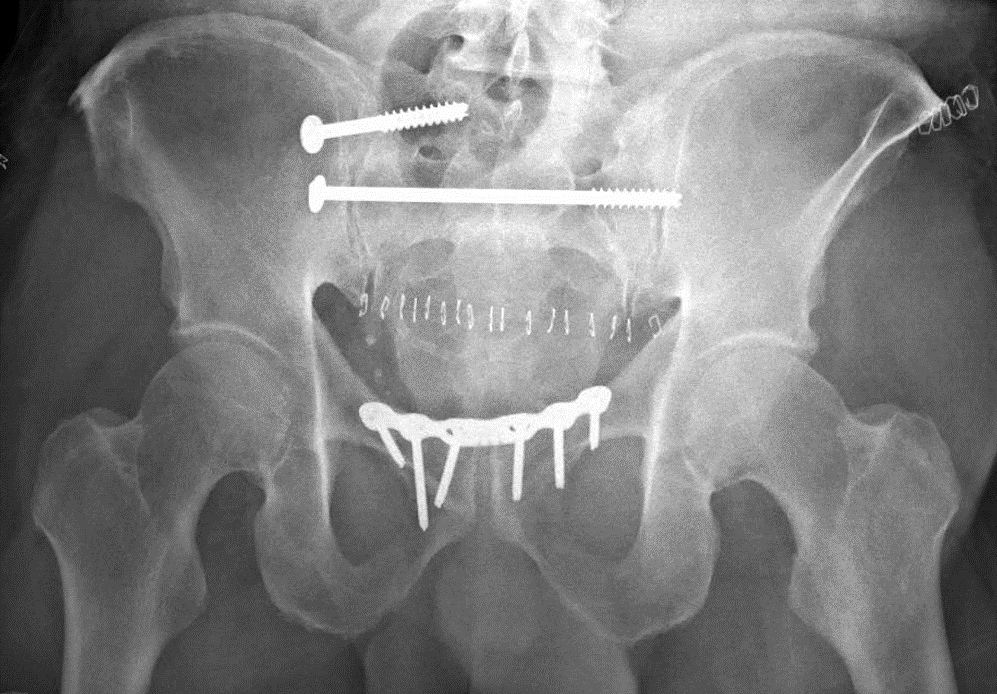

Postoperative radiograph in this patient.